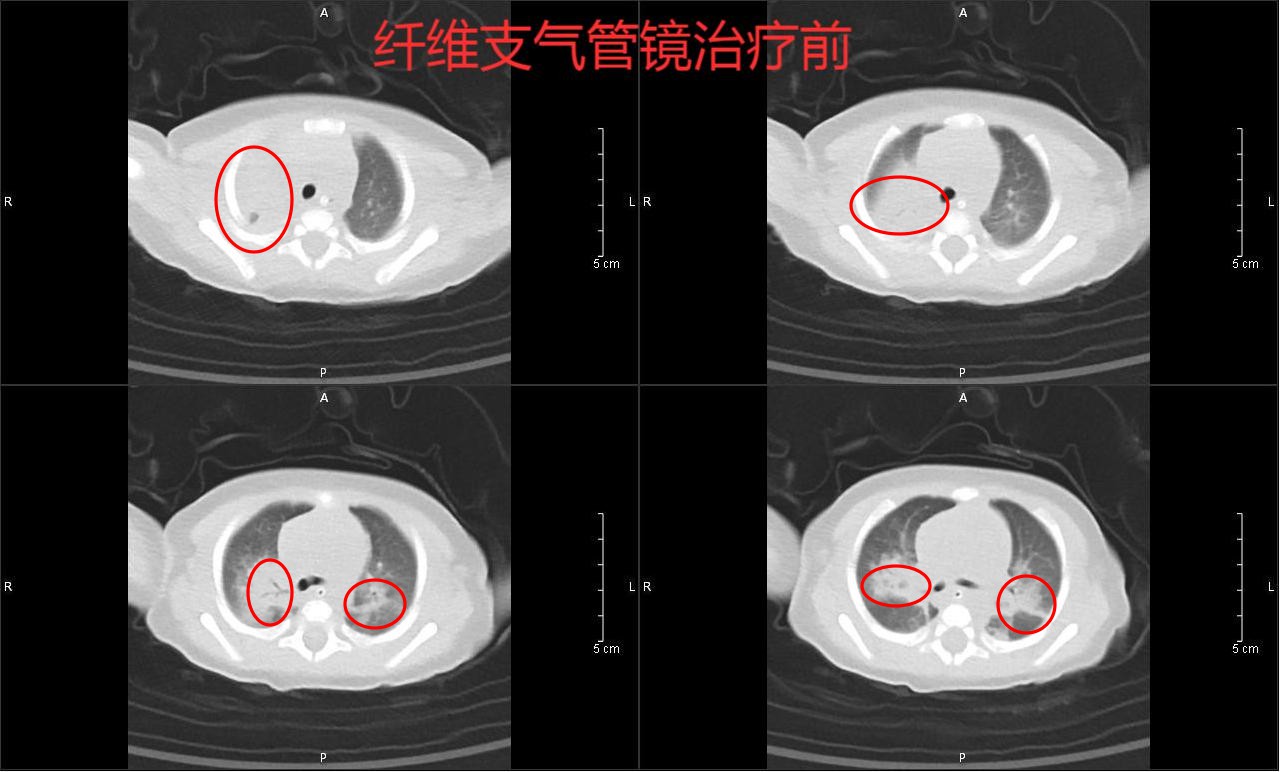

治疗前

由于患儿右肺不张及肺部大量炎症不容乐观,可能导致患儿再次出现呼吸、心力衰竭,为进一步清除肺部炎症,韦瑞含副主任医师给患儿进行了纤支镜检查及肺泡灌洗。7天后当小滢双肺病灶明显吸收,疗效显著,于1月18号转普通病房继续治疗。后经过近半个月的积极治疗,小滢终于康复出院。